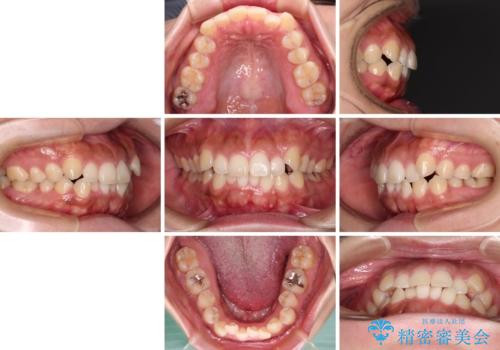

【モニター】カリエール・ディスタライザーを併用した八重歯のインビザライン矯正

- 1年8ヶ月

- 10-30回

- 治療費の目安: 100万円(税込)費用は治療当時の料金となります

カリエールディスタライザーを併用したことで、すっきりとした口元になり、上下の正中を合わせることができました。